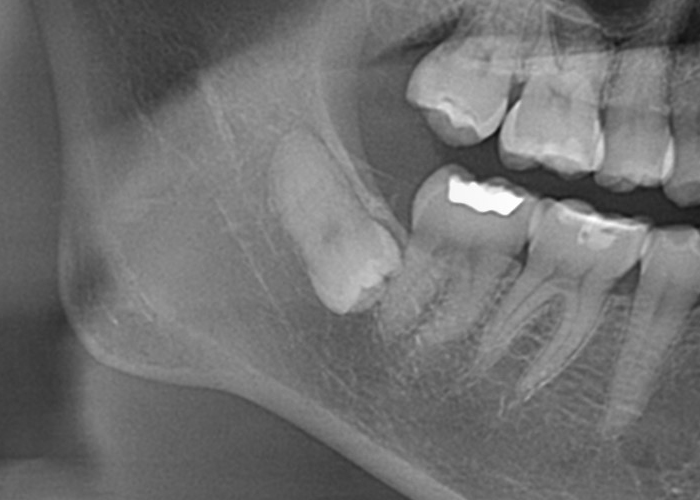

パノラマX線写真を撮影し親知らずの位置関係を把握します。

深さによってはCTまで撮影し3次元的な位置関係の把握を行います。その後局所麻酔と口腔内の清掃を行った上で抜歯します。

親知らずの頭や周囲の骨が引っかかって抜きづらい場合は親知らずを分割したり、周囲の骨を部分的に削除しながら親知らずの抜歯を行います。